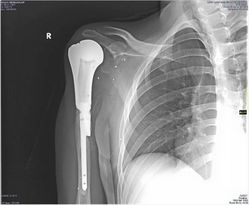

Doç. Dr. Halil Can GEMALMAZ - Vakası